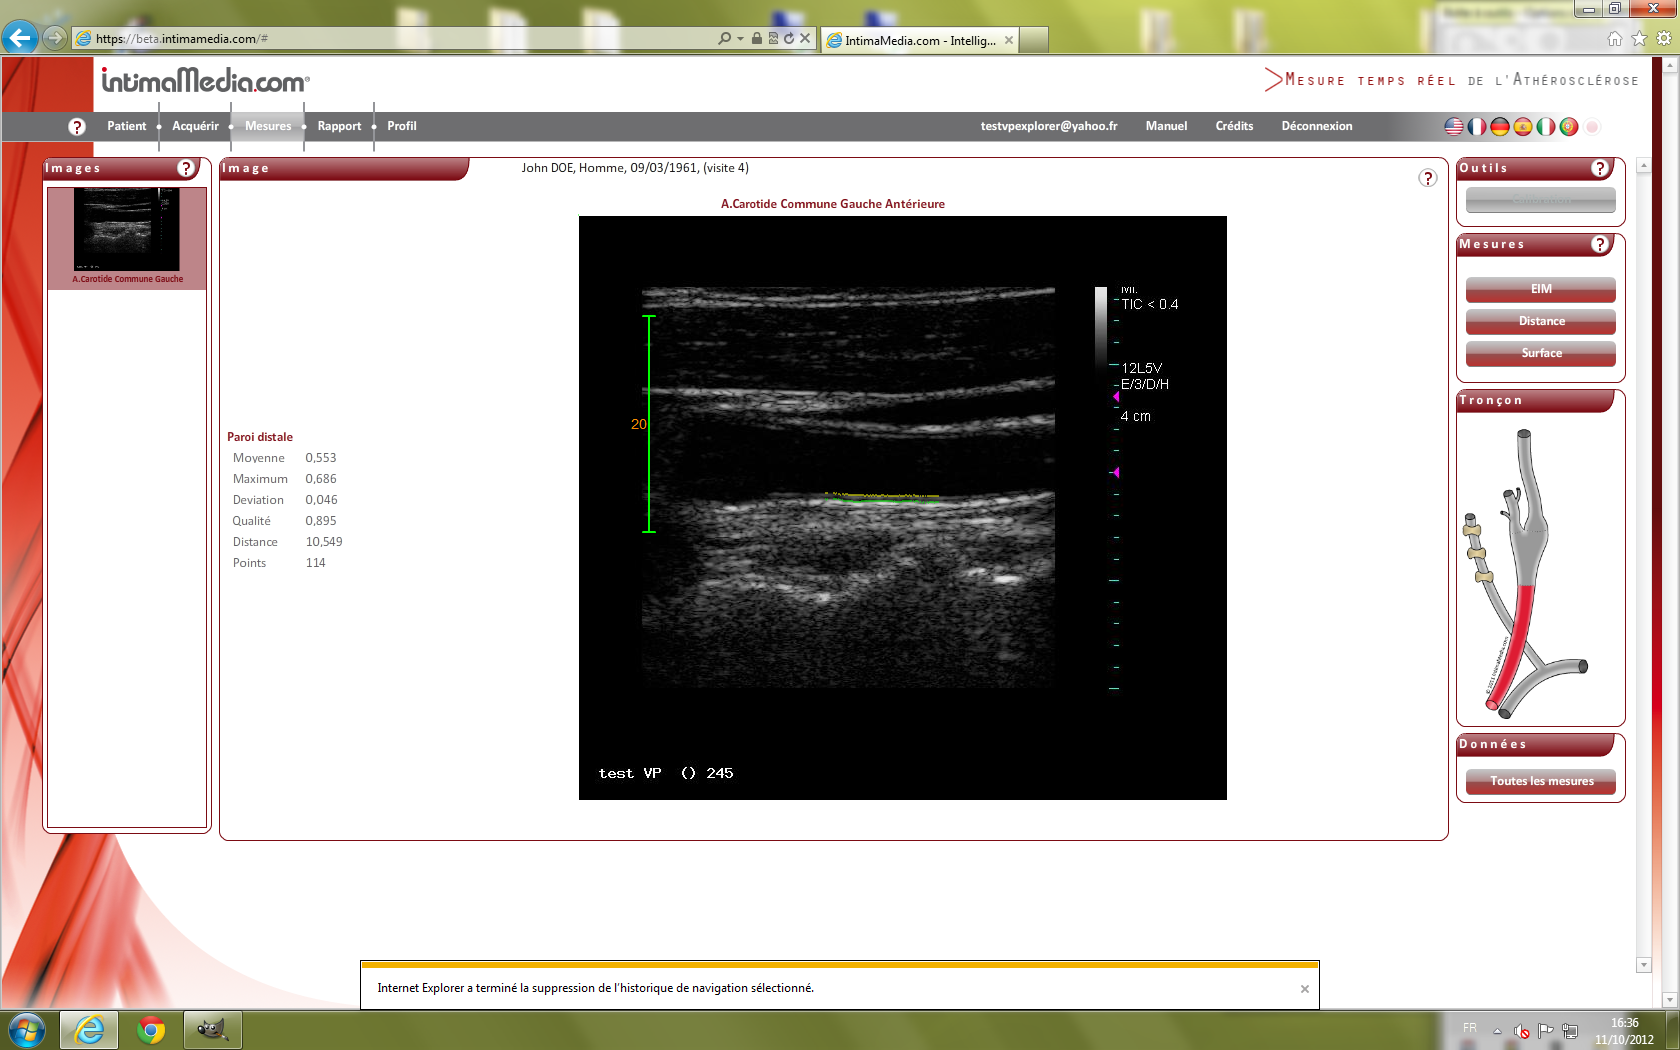

Images VP IExplorer 9. IntimaMedia 2.0.0 Fonctionnal

EchelleDicomImage.png

526 KB